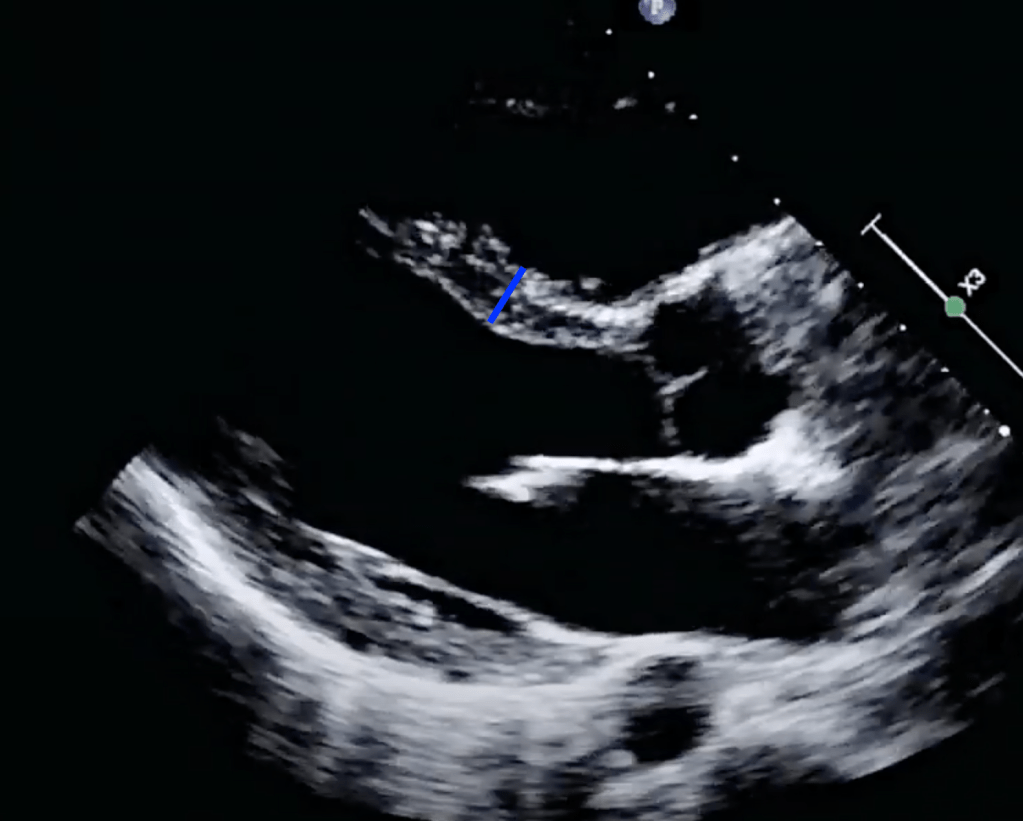

Looking at the initial EKG, you are concerned that this is possibly Wellens syndrome with Wellens waves in V2 and V3. While awaiting for cardiology to arrive, you obtain a bedside echo:

The bedside echo shows a reduced ejection fraction and looking through your records this is new when compared to his last echo.

The mitral valve in a structurally normal heart should approach the septum during ventricular contraction. Below is a normal echo. Look how the mitral valve “slaps” the septum during each contraction. Go back to our image above and see that the mitral valve does not approach the septum during contraction.